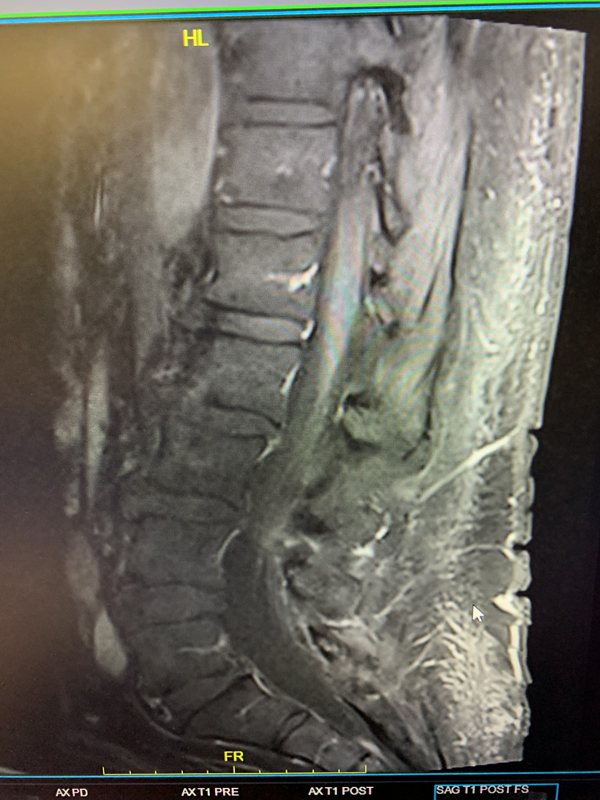

Based on the MRI findings and the clinical presentation, a spinal dural fistula was presumptively diagnosed and a spinal angiogram recommended with planned attempt to embolize a fistula if encountered. Spinal angiography confirmed a spinal dural fistula fed from radiculomedullary branches off the left T6 pedicle and draining into a spinal vein (Figure 2B & 2D).

No spinal arteries were identified from this pedicle and after provocative testing with lidocaine and amytol injection confirmed that no arterial input to the spinal cord, the fistula was sealed with one injection of onyx glue (Figure 2C). Post-embolization angiogram confirmed no residual filling of the fistula (Figure 2D).

Pre-Treatment (Figure 2A and 2D), At Treatment (Figure 2B – Onyx Glue Cast), and PostTreatment (Figure 2C)